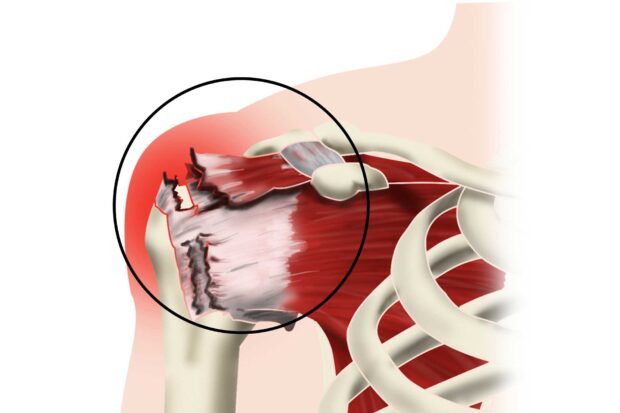

La butée de Latarjet est une technique chirurgicale qui vise à stabiliser les épaules instables. Elle est très efficace comparativement à d’autres techniques. Cette vidéo vous montre en images sa réalisation au bloc opératoire.